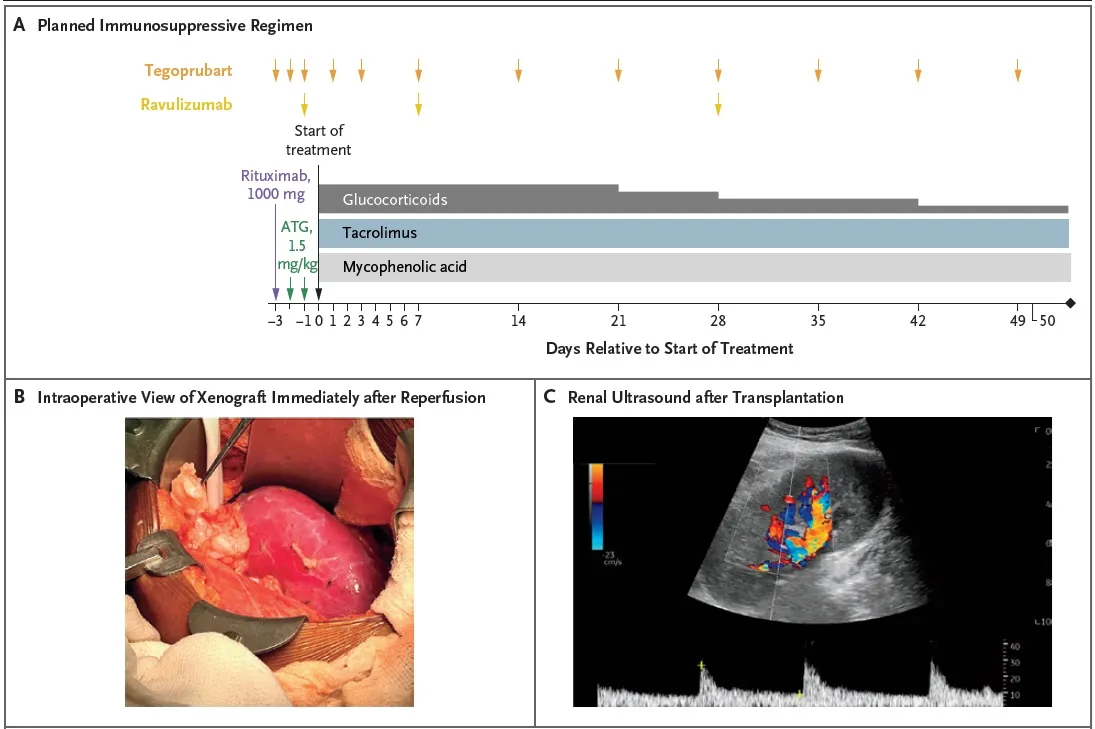

Xenotransplante Renal: um marco no Transplante!